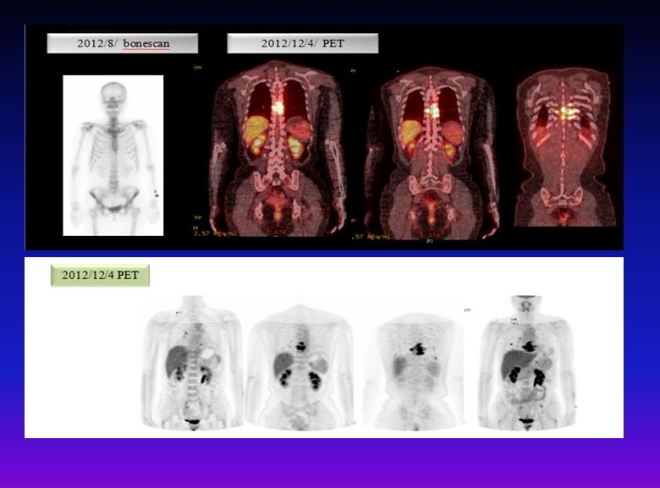

나이가 50대 후반인 여성 환자 분이 옆구리의 통증으로 한의원을 찾았다. 이분은 암환자들에게 등록할 때 필요한 서류를 작성하라고 하였더니 한사코 이를 거절하였다. 두 부부가 똑같이 나는 암환자가 아닌데 왜 암환자로 취급하느냐 하고 간호사 선생님들하고 말다툼을 하였다. 나는 바깥이 시끄럽길래 무슨 사연인지하고 직접이야기를 들어보았다. 사연인즉 2012 년 2월 오른쪽 가슴에 몽울이 생겼는데 큰병원에서 유방암 1기 초이고 임파전이가 없다고 하면서 선생님이 부분절제와 전절제의 두가지 방법이 있다고 하셨다. “부분절제를 하면 방사선과 항암을 해야 합니다. 그리고 만약 전절제를 하면 이런 조치는 필요가 없습니다.”  Y 대학 병원에서 치료를 받았는데 항암제의 부작용을 익히 들어오던 터라 환자는 전절제를 택하였다. 그리고 암이 완치된 줄 알고 지냈는데 여름철이 되자 옆구리가 아프기 시작하였다. 그래서 담당선생님한테 이야기하고 bonescan (뼈의 전이를 보는 촬영방법)을 하였는데 정상소견이 나왔다. 그래도 본인이 아파하자 정형외과 재활외과 신경내과 등을 전전하였다. 몇 달간 치료를 해도 증상이 나아지지 않았다. 그래서 결국 11월쯤 되어서 본원에 찾아오게 된 것이다.  8월달 시행한 bonescan 에서 이상이 없다 하니, 환자는 암에 의한 통증이 아닌 줄 생각하고 있어서 다른 치료법을 찾았지만  뾰족한 개선이 없게 되자 한의원까지 오게 된 것이었다. 당시 내 경험으로는 환자가 호소하는 통증이 벌써 뼈전이 내지 흉막전이가 된듯 하였다. 그래서 방사선과에 의뢰하여서 폐사진을 찍게 하였는데 폐에도 의심스러운 점이 보였다. 그래서 환자에게 pet-scan을 추천하였고, 환자는 결과를 가지고 다시 방문하였다. 결과는 다발성 폐전이와 뼈전이가 된 상태였다. 이러한 당황스러운 결과가 나오자 수술하였던 선생님에 대한 믿음이 사라졌고 우리 쪽의 치료방법을 따르기로 하였다.

6-4

그림1 좌측 사진은 bonescan으로 별 다른 이상이 보이지 않는다. 우측 사진은 내원 초기에 찍은 PET로밝은 음영이 척추에 보이는 부분이 종양이 전이된 부분이다. 폐에는작은 nodule이 수많이 점점으로 있는데 이 사진에서는 보이지 않는다. 이 환자는 herceptin 수용체가 있는 경우여서 초기에 taxol과 herceptin을 생각하였으나 나의 권고에 의해서 taxol은 사용치 않고  CAF 이후에 herceptin을 사용하기로 하고 협진하는 병원에 의뢰하여서 이 방법을 한방치료와 같이 시행하였다. 내원 초기에 CT에서  소견서에 따르면 multiple small nodules both lungs hematogeneous metastasis likely –수많은 작은 종양들이 양쪽 폐에 보인다. 혈행성전이로 판단된다. 이밖에도 척추에도 전이가 되어 있었고 골반부위에도 전이가 되었고 임파절도 여러 군데 전이가 보였다. 그리고  4개월 뒤에 결과는 다음과 같이 좋아졌다.

6-5

그림2  위의 사진은 역시 PET 사진으로 척추 아래 왼쪽으로 간이 보이고 그 아래에 검은 음영은 조영제가 신장으로 내려가는 부분으로 정상 부위이다. 여기를 제외한 제일 우측 사진에서 보이는 오른쪽 어깨의 점이 목의 림프절 전이이고 이밖에도 좌측 골반 부위에도 자세히 보면 검은 점이 나타나는데 이 부분 역시 종양이 전이된 부분이다. 중간에도 오른쪽으로 간 위에 점이 보이는 부분이 7th갈비뼈에 전이가 된부분이다.  2012년 12월 4일에 비해서 치료초기 2013년 1월 24일 아래의 중간 사진을 보면 음영이 많이소실이 되어 있고 치료 5개월 뒤인 제일 우측 사진에서는 종양의 흔적이 잘 안 보인다. 환자는 한양방 통합치료 한 달 뒤에 종양이 확연히 줄어들기 시작하였다. 두 달 뒤 PET에서 흉추 7번과 왼쪽 갈비뼈 7번의 뒤편 그리고 흉추 6번 등에 아직은 조영증가 소견을 보이지만 2012년 외부 필름에서 보이던 오른쪽 경부의 림프절과 양쪽 폐의 종양과 왼쪽 골반은 호전되어서 보이지 않게 되었고 이후에도 더욱 종양이 줄어들었다